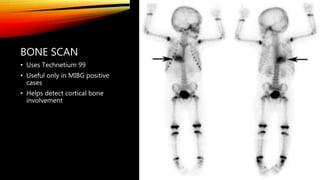

BONE SCAN

• Uses Technetium 99

• Useful only in MIBG positive

cases

• Helps detect cortical bone

involvement